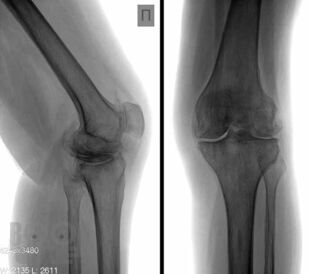

В основу книги положен многолетний опыт исследований коленного сустава в многопрофильной клинике с развитой ревматологической и ортопедической службами. Авторами приводится непредвзятое освещение возможностей современных методов лучевой диагностики патологии коленного сустава с адекватным позиционированием ультразвуковых исследований на различных этапах оказания медицинской помощи. Проанализирован опыт отечественных и зарубежных авторов, суммированы результаты многочисленных оригинальных собственных исследований. Подробно освещены особенности ультразвукового исследования широкого спектра патологических состояний и заболеваний травматического, воспалительного генеза, встречающихся у молодых и пожилых пациентов.

В книге представлен большой иллюстративный материал. Подробно изложена топографическая и ультразвуковая анатомия коленного сустава, рассмотрены технические особенности проведения исследования, варианты визуализации многочисленных патологических изменений.